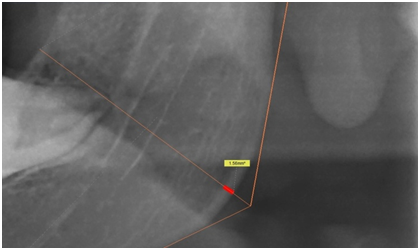

1. Gonial Angle (GA): It was assessed by tracing one line tangent to the lower border of mandible and another line tangent to the posterior border of the ramus of mandible, which was proposed by Mattila et al.2 The intersection of these lines forms the gonial angle (Figure 1).

Figure 1 The radiographic representation of the Gonial angle (GA) obtained by measuring the angle between the tangents drawn at the lower border of mandible and the posterior border of the ramus of mandible.